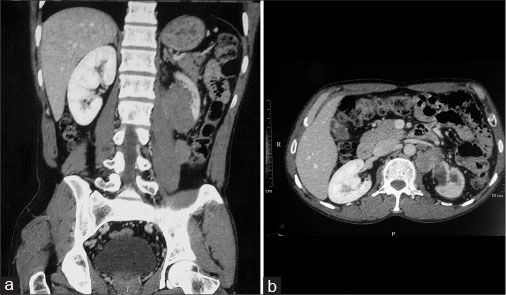

A 40-year-male was admitted with chief complaints of swelling in the left flank and abdominal discomfort for 2 years. The swelling was gradually increasing in size and was not associated with fever, hematuria, or constipation. The patient was a chronic smoker. Hematological and biochemical investigations were within normal limits. X-ray chest was normal. Ultrasonography abdomen suggested a left renal mass with tumor emboli in the left renal vein and inferior vena cava lumen. Computed tomography abdomen was done and showed left renal mass at the lower pole with complete encasement of ipsilateral ureter, renal artery, and vein. Tumor was extending medially up to the aorta with mild paravertebral extension at L2 into the para-aortic lymph nodes and infiltration of the psoas muscle and colon [Figure 1]. Fine needle aspiration cytology was done from outside which showed single and small groups of atypical cells with eccentric hyperchromatic nuclei and focally appreciable vacuolated cytoplasm against a hemorrhagic background. Cytological diagnosis was malignant tumor with a possibility of clear cell renal carcinoma.

| Figure. 1 (a) Magnetic resonance imaging showing a large relatively well-defined irregular shape, heterogeneously enhancing mass lesion with delayed filling seen in the perinephric and renal capsular region at the lower pole of the left kidney. (b) Mass is causing complete encasement of renal artery and vein